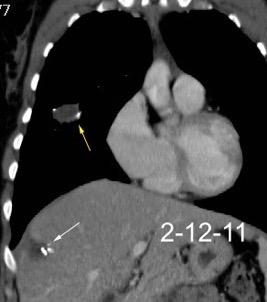

31. ENFERMEDAD TORACOABDOMINAL. TUMOR

T. mixto de células germinales del testículo izquierdo

Nódulos pulmonares múltiples. (flechas verdes). Masas paratraqueales. (flechas amarillas). Dudoso ensanchamiento retrocrural (flechas negras). sigue….

Ttawfik A et al. Trans-diaphragmatic Pathologies: Anatomical Background and Spread of Disease on cross-sectional Imaging. Current Problems in Diagnostic Radiology. 2021.

T. mixto de células germinales del testículo

izquierdo Metástasis pulmonares. (flechas verdes). Ganglios paratraqueales. (flechas amarillas). Ganglios retroperitoneales (flechas negras)

Tawfik A et al. Trans-diaphragmatic Pathologies: Anatomical Background and Spread of Disease on cross-sectional Imaging. Current Problems in Diagnostic Radiology. 2021.